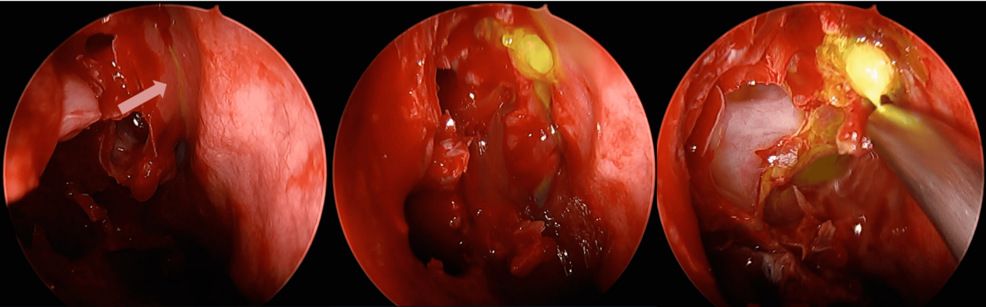

Invasive aspergillosis (IA) remains a serious and often fatal infection despite advances in diagnostics and antifungal therapy. Although mold-active triazoles have long been recommended as first-line therapy, liposomal amphotericin B continues…